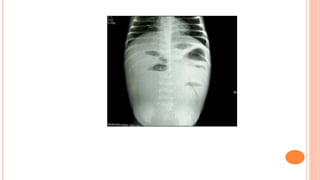

Acute abdomen series in a child with intussusception

provides the picture of multiple dilated intestinal loops with

step-ladder pattern of air fluid leve

Case 1 A 6-month-old,previously healthy boy was brought to the ED for clear emesis of 1 day. No history of fever, diarrhea, irritability or trauma. On exam the child appeared well, with normal vital signs and with a benign physical exam. Abdomen was soft to palpation with normal bowel sounds. The patient was treated in the ED as a viral gastritis. He tolerated oral fluids well and was discharged home. Parents returned because emesis continued. On his second visit, a rectal exam revealed occult blood in stools. He was taken for abdominal x-rays which showed a questionable mass on the right lower quadrant (RLQ) suggestive of intussusception. Barium enema failed to reduce the mass and the child was taken to the OR with uneventful course.

Acute abdomen seriesin a child with intussusception provides the picture of multiple dilated intestinal loops with step-ladder pattern of air fluid leve